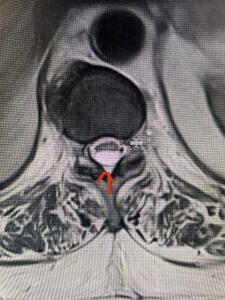

This 47-year-old male who four months prior was lifting weights developed sharp pain in his neck. After that he developed progressive numbness in his arms, neck pain and headache. He said that the right arm was worse than the left. On examination the patient had long tract weakness on the right side which included his triceps, finger extensors, hip flexors, and dorsiflexors. The patient did not have hyperreflexia. MRI (Fig. 2) demonstrated a massive, extruded disc herniation with severe cord compression. The patient because of progressive myelopathy and spinal cord compression was indicated for anterior cervical discectomy and fusion at C4-5 (Fig. 3). Patient had significant improvement of weakness and numbness post operatively.

Fig: 2b Axial T2-weighted cervical MRI demonstrating spinal cord compression from C4-5 herniated disc (red arrow)